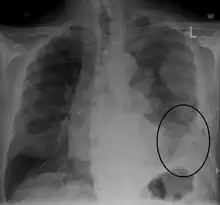

CXR demonstrating a mesothelioma